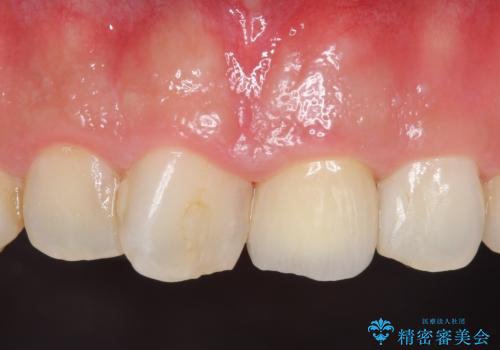

オールセラミッククラウン 長さが気になる前歯の改善

御希望された再根管治療終了後、オールセラミッククラウンによる補綴を行いました。

今回用いたオールセラミッククラウンはジルコニアフレームという白い素材の上にセラミックを盛っているため、審美性が非常に高いのが特徴です。

また、ジルコニアは人工ダイヤモンドの材料にも使われているほど高い強度を持っており、そのためオールセラミッククラウンは審美性だけでなく、奥歯やブリッジの補綴も可能とするクラウンです。